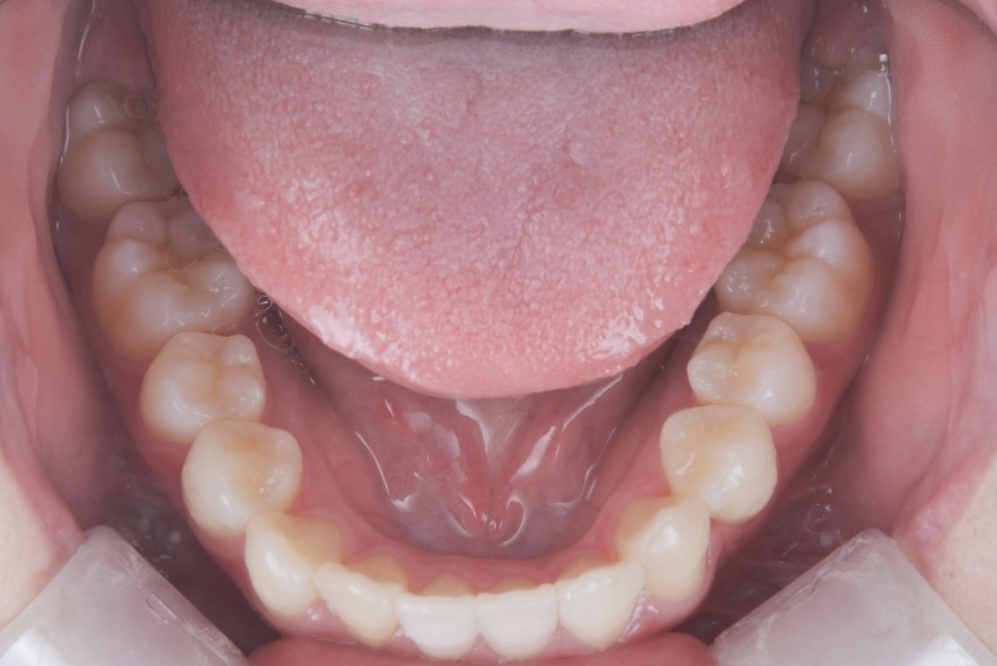

高校生女性 八重歯と噛み合わせが気になる

高校生の女性の患者さまで、初診時は15歳でした。八重歯と噛み合わせの乱れを主訴にご相談に来院されました。歯並びについて意識するようになったきっかけは、学校の歯科健診で矯正治療をすすめられたことだったそうです。

八重歯や噛み合わせが整い、口元の印象が大きく改善しています。治療後には、矯正中のモチベーション維持や経過確認がしやすかった点、想定よりも早く治療を終えられたことについて、嬉しい口コミもお寄せいただきました。

BEFORE

AFTER